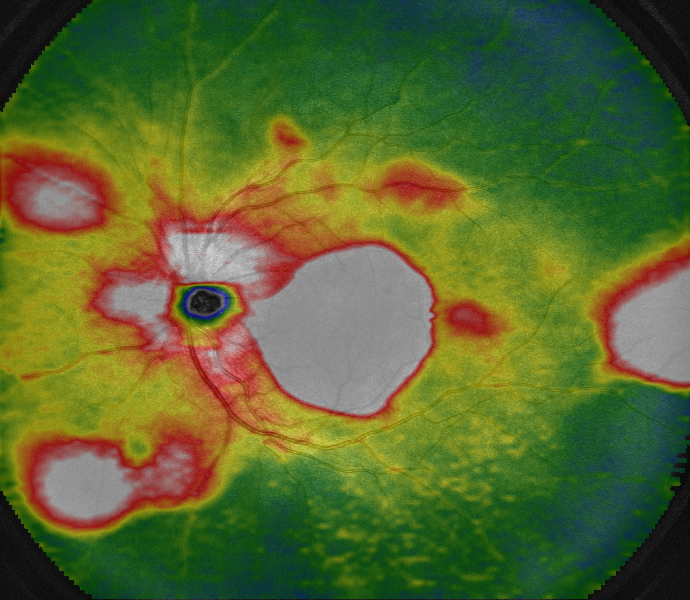

OCTA(アンギオグラフィ-)機能

造影剤を使わずに、網膜と脈絡膜の血管を鮮明に映し出すことができます。血流の状態を詳しく調べられます。